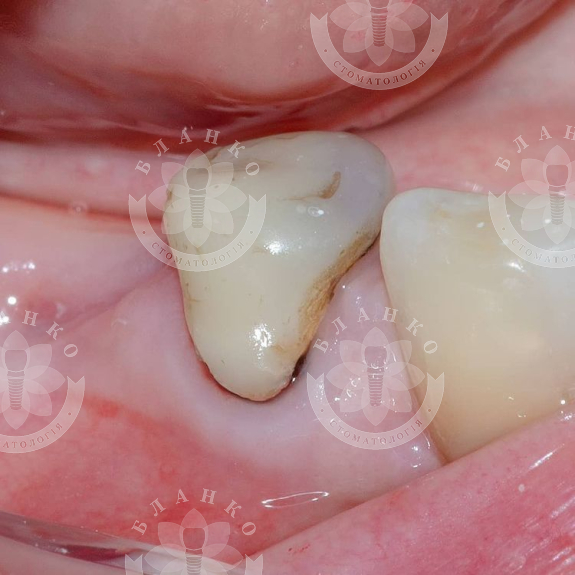

Повторное эндодонтическое лечение вторичного кариеса перед перекрытием зуба непрямой реставрацией 👍💙🎉